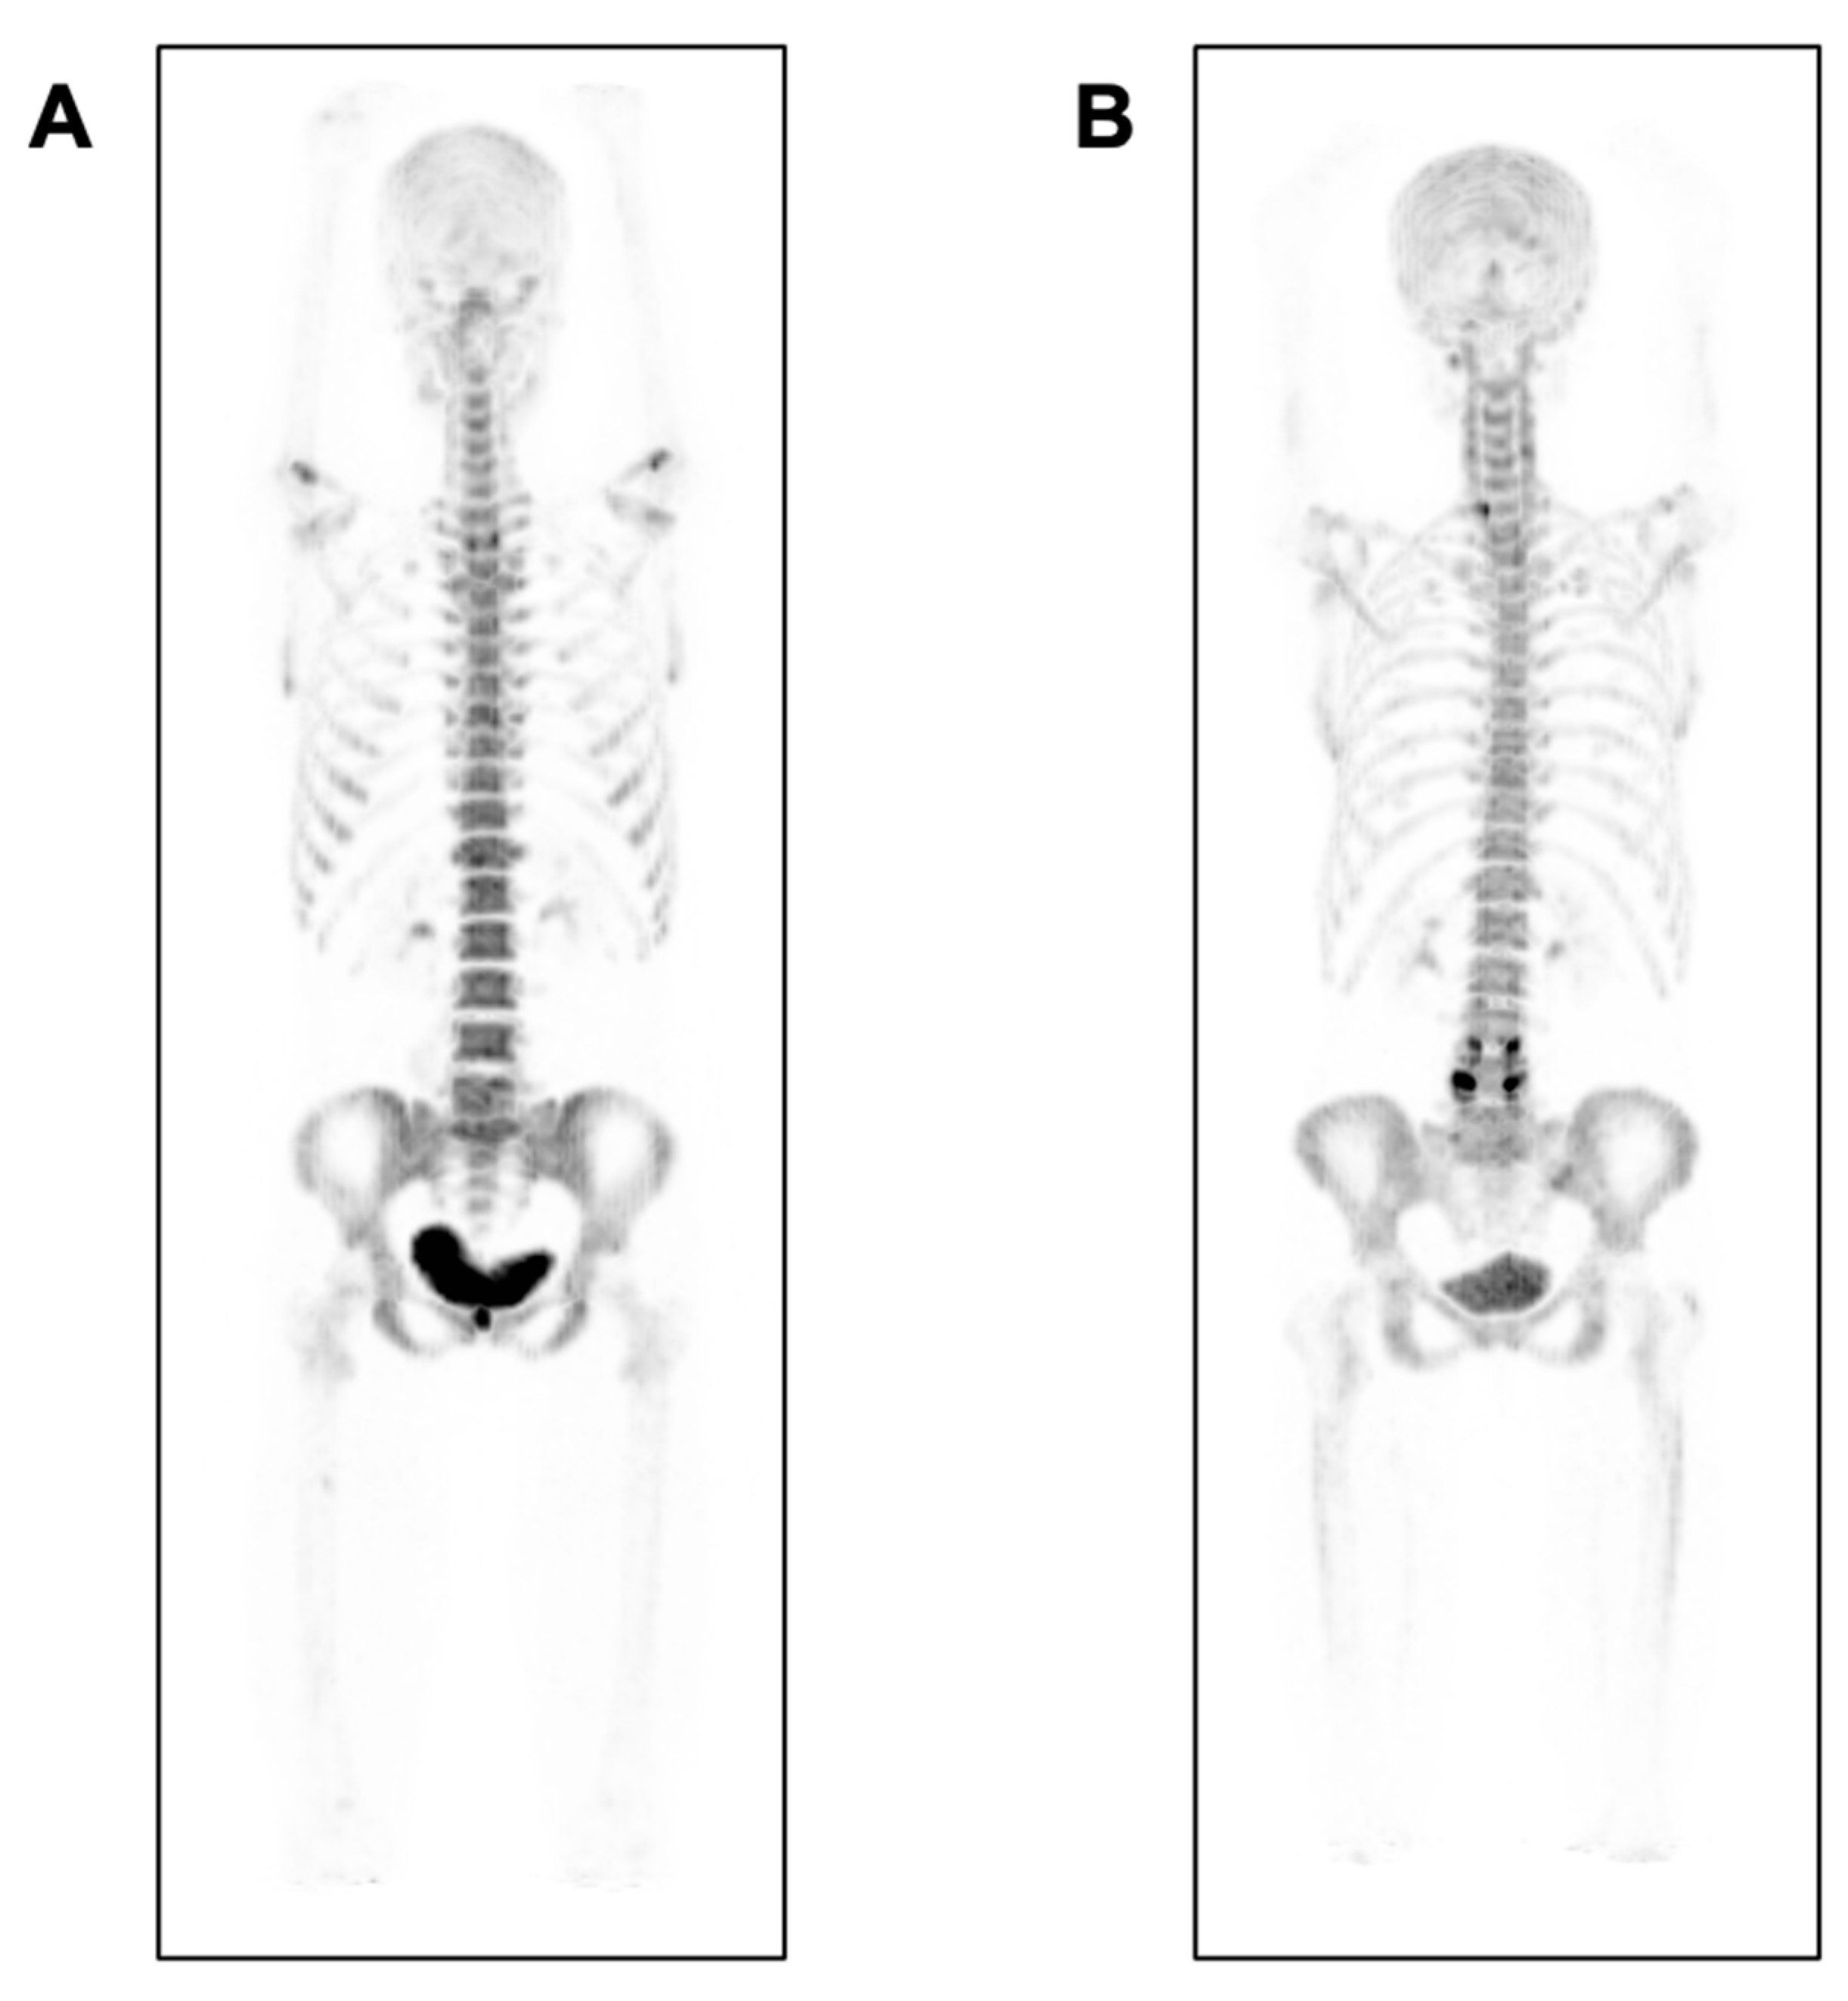

- Botman, E.; Raijmakers, P.; Yaqub, M.; Teunissen, B.; Netelenbos, C.; Lubbers, W.; Schwarte, L.A.; Micha, D.; Bravenboer, N.; Schoenmaker, T.; et al. Evolution of heterotopic bone in fibrodysplasia ossificans progressiva: An [(18)F]NaF PET/CT study. Bone 2019, 124, 1–6. [Google Scholar] [CrossRef] [PubMed]